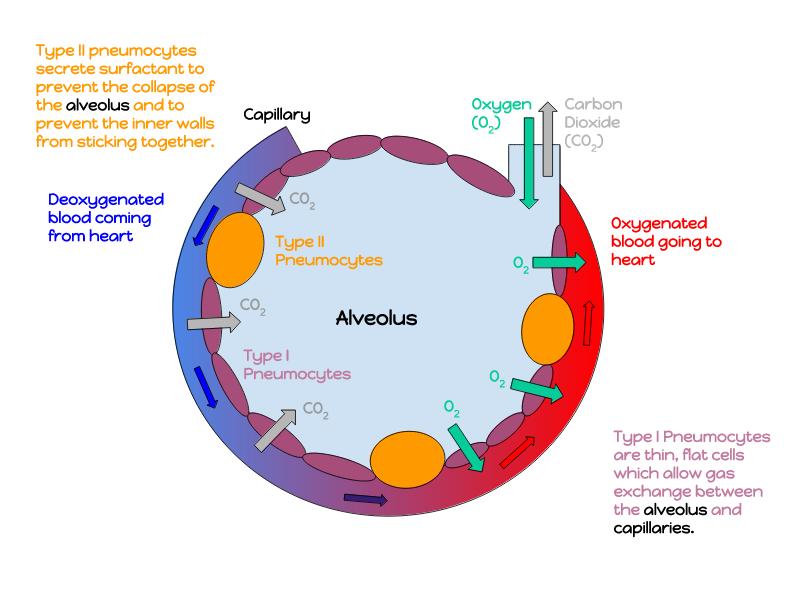

The cardiovascular system needs to be connected to the respiratory system.Path of O2 and CO2

- List complete

- With layers

- And cells

- And function of each

Components of the Blood-Air Barrier?

What other barrier systems are found in the body?

What are the purpose of each of these barrier systems? Connected with physiology will unlock the pathology.

- Alveoli